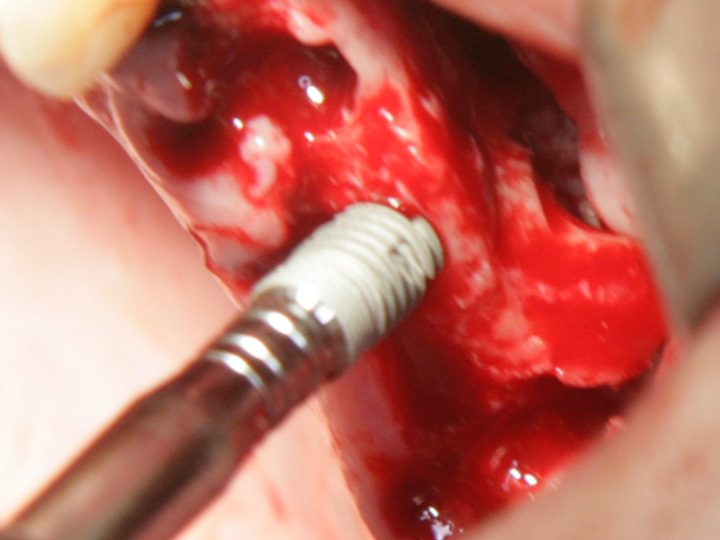

Отворен максиларен синус в началото на интервенцията. Случаят е интересен със следното - твърде атипична форма на трепанационния отвор. На какво се дължи на това - на лошо планиране на оперативния достъп или на нещо друго? Дължи се на факта, че отначало въпросната намеса беше планирана като балонен синуслифт; за съжаление обаче мембраната на синуса се разкъса и надуването на балона стана невъзможно.